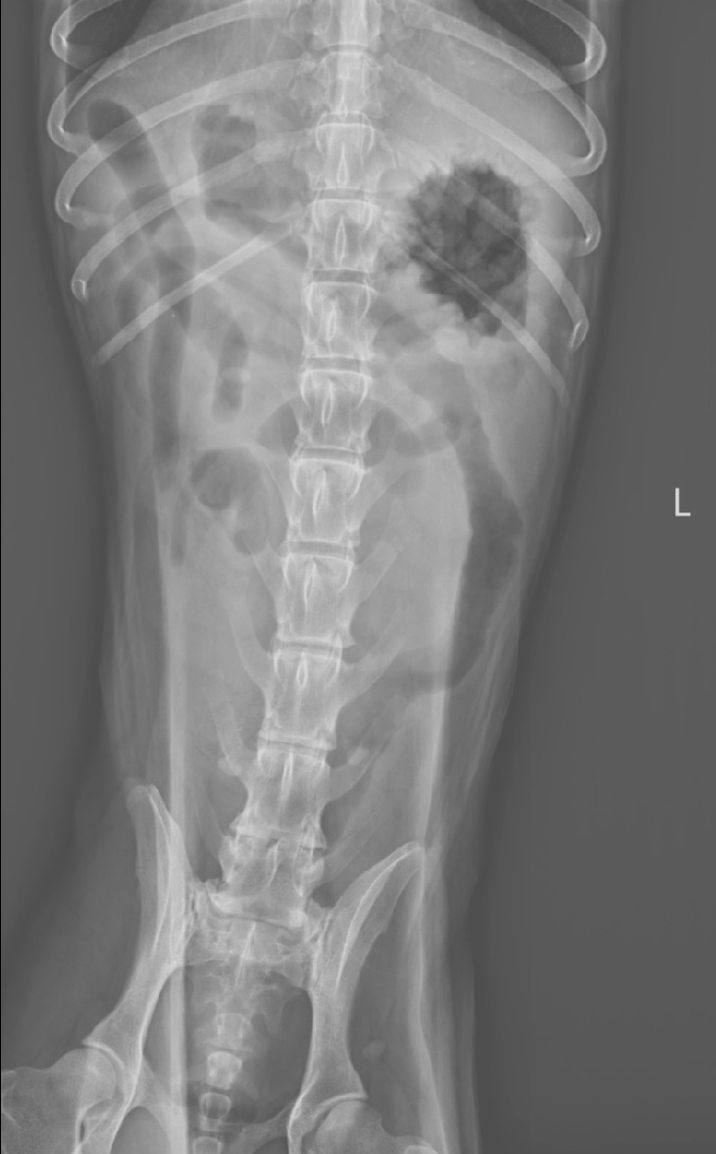

L’examen radiographique met en évidence :

- La présence de deux populations d’anses intestinales grêles de diamètres différents :

- certaines vides

- d’autres dilatées par du gaz et du liquide

Cette distribution est évocatrice d’un iléus mécanique

- Un contenu digestif grêle atypique, visible à droite de la ligne médiane au niveau de L5–L6, caractérisé par un aspect réticulé mêlant gaz et opacité tissulaire

L’aspect est compatible avec la présence d’un corps étranger intraluminal

- Le côlon est modérément dilaté par du gaz

- Une spondylose déformante marquée entre L6 et S1, ainsi qu’entre L6 et L7

Les images sont compatibles avec une obstruction mécanique de l’intestin grêle, très probablement secondaire à la présence d’un corps étranger intraluminal, dont l’aspect est fortement suspect d’un trognon d’épi de maïs.

La spondylose lombo-sacrée observée correspond à une lésion dégénérative chronique incidente, sans lien avec le motif de consultation.

Chez le chien, un rapport entre le diamètre maximal d’une anse grêle dilatée et la hauteur du corps vertébral de L5 supérieur à 1,95 est fortement suggestif d’une obstruction mécanique (80%).